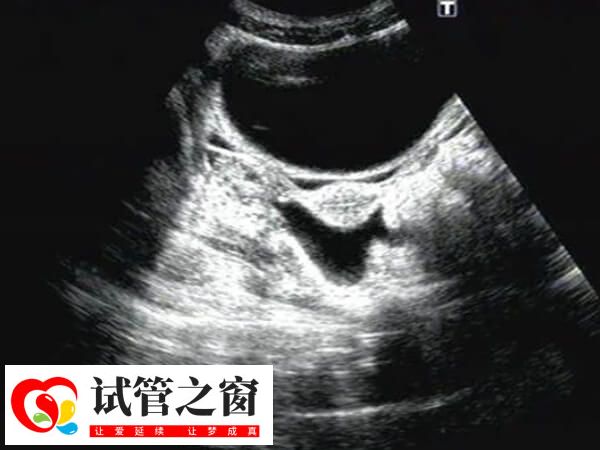

盆腔积液是女性生殖系统的常见症状表现,它不是一种疾病,确切地说是影像学对盆腔内液体的一种描述。正常情况下,患者做试管取卵后出现盆腔积液,那么可能会引起以下身体不适: